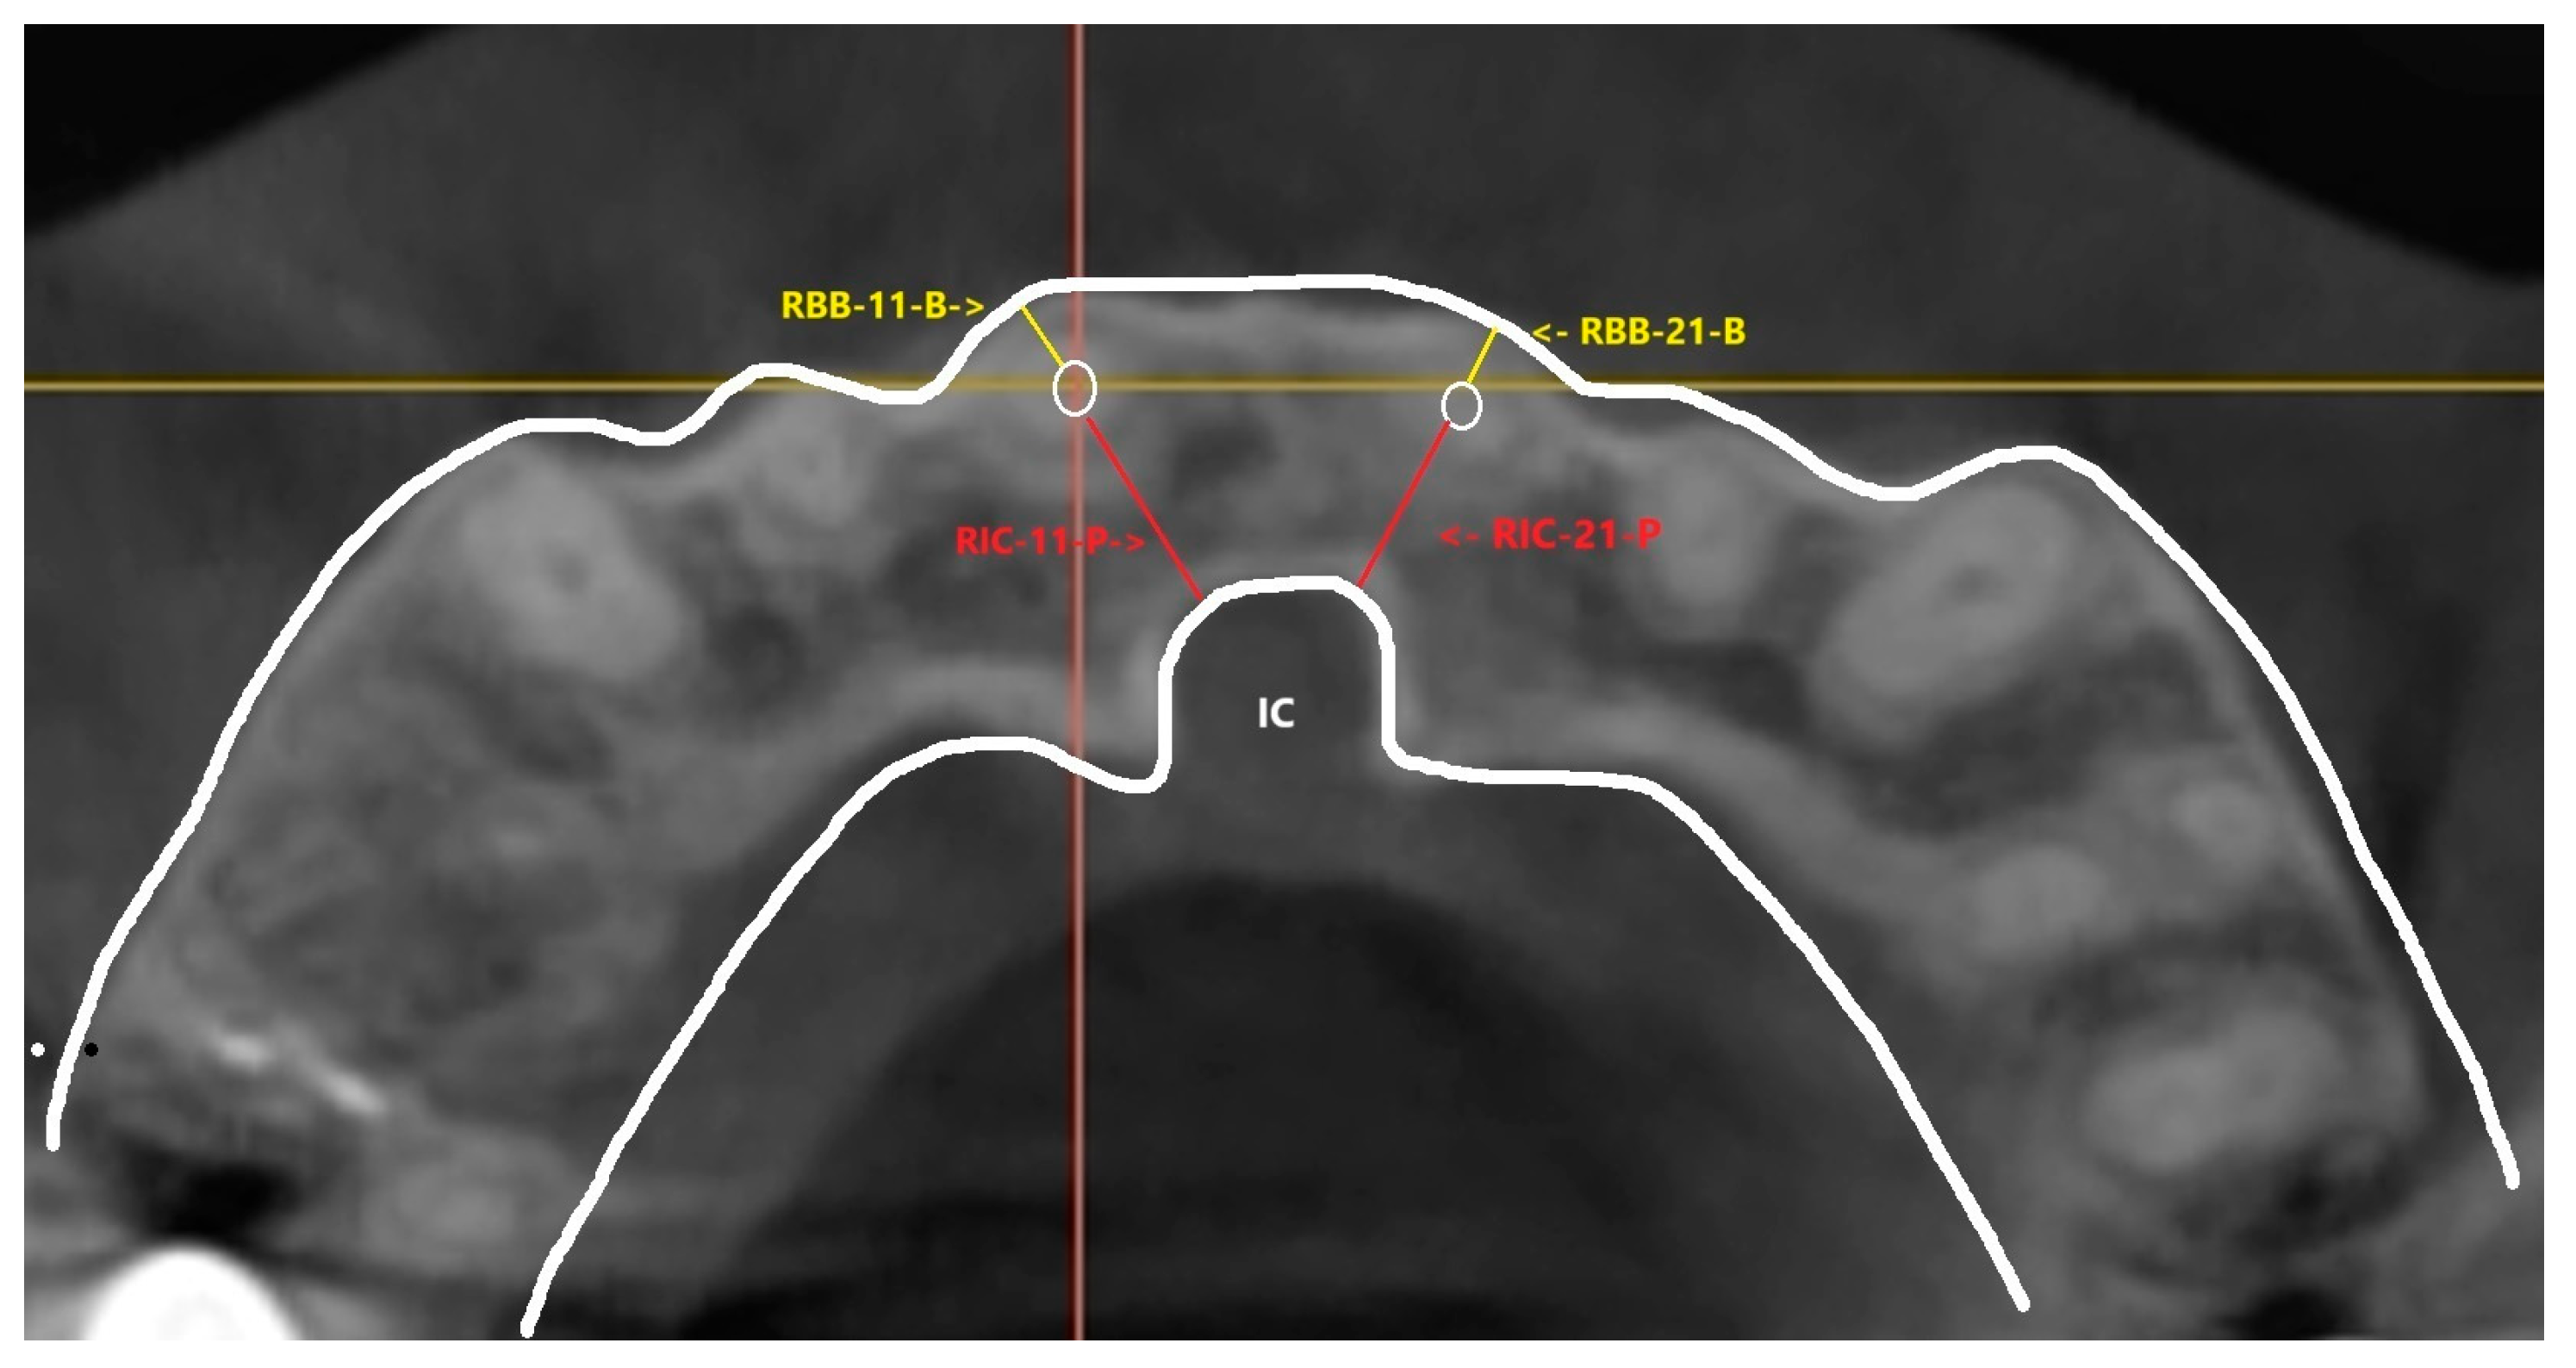

This perpendicular line was transferred to the axial slices of the CBCT image to set the axial slices horizontal to this reference. From the axial slices where root apex of central incisors are located, linear measurements of the shortest distance between the IC and each maxillary central incisor root apex were performed, defining thickness of the available palatal bone—marked as RIC-11-P and RIC-21-P for right central incisor 11 and the left central incisor 21, respectively. Shortest distance between each central incisor root apex and the buccal bone border was measured, defining thickness of the buccal bone at the apical level—marked as RBB-11-B and RBB-21-B for right central incisor 11 and the left central incisor 21, respectively. (Figure 3 and Figure 4) Similar linear method of measurement on axial slices of CBCT was observed in a study by Ishii T et al., 2023 [19].

Figure 2. These are the root apexes of central incisors, and the linear distances are labelled as RIC-11-P and RIC-21-P (red) for root apex to incisive canal and RBB-11-B and RBB-21-B for root apex to buccal bone.